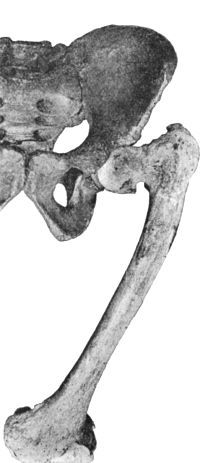

| 129. | Innominate Bone and Upper End of Femur from a case of Congenital Dislocation of Hip | 250 |